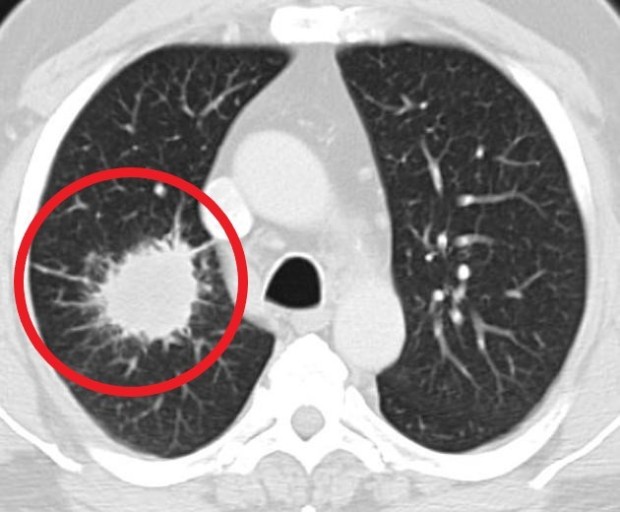

폐암 초기증상 4. 기침

폐암 초기증상 다음은 기침입니다. 이것은 호흡곤란과 이어지는 증상인데요. 기침은 가장 흔하게 발생하는 폐암 초기증상입니다. 기침 사실 감기나 천식, 최근에는 코로나 증상 등의 다른 호흡기 질병에서도 흔히 발생하는 증상이라 처음에는 대수롭지 않게 여기고 넘어가는 그럴 경우가 많습니다. 하지만 계속하여 기침 증상이 끊이지 않는다면 폐암 체크를 받아보는 게 좋습니다.